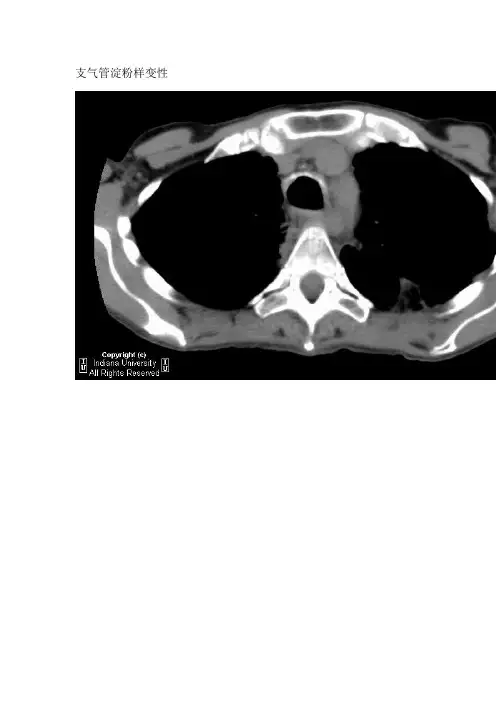

支气管淀粉样变性

气管支气管淀粉样变的影像学表现反映了其病理改变,可以是单发的肿物,也可以是弥漫性的气管狭窄。

CT上可以表现为肿块、斑块或气管、主支气管、叶支气管及段支气管壁环状增厚,伴有部分或完全性管腔狭窄。

有时还可表现为增厚的气管支气管壁结节和钙化。

胸部CT如图1示:气管下段及左、右主支气管狭窄;左右主支气管黏膜下钙化。